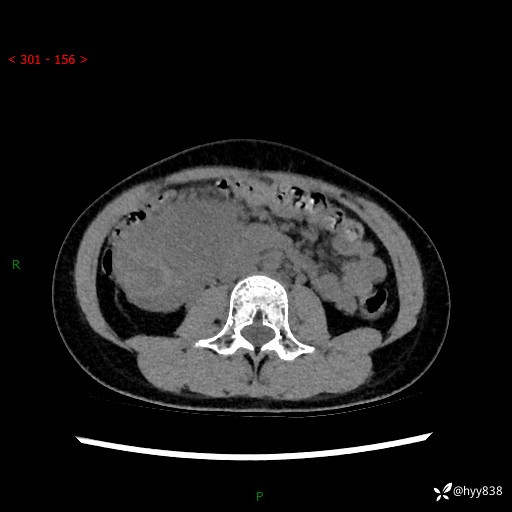

病例小姑娘,超声提示上腹部巨大包块。平扫就能轻松搞定的病变--结果公布

性别:女

年龄:13岁

简要病史:超声提示上腹部巨大包块

上腹部CT平扫

胰腺实性假乳头状瘤 (17)